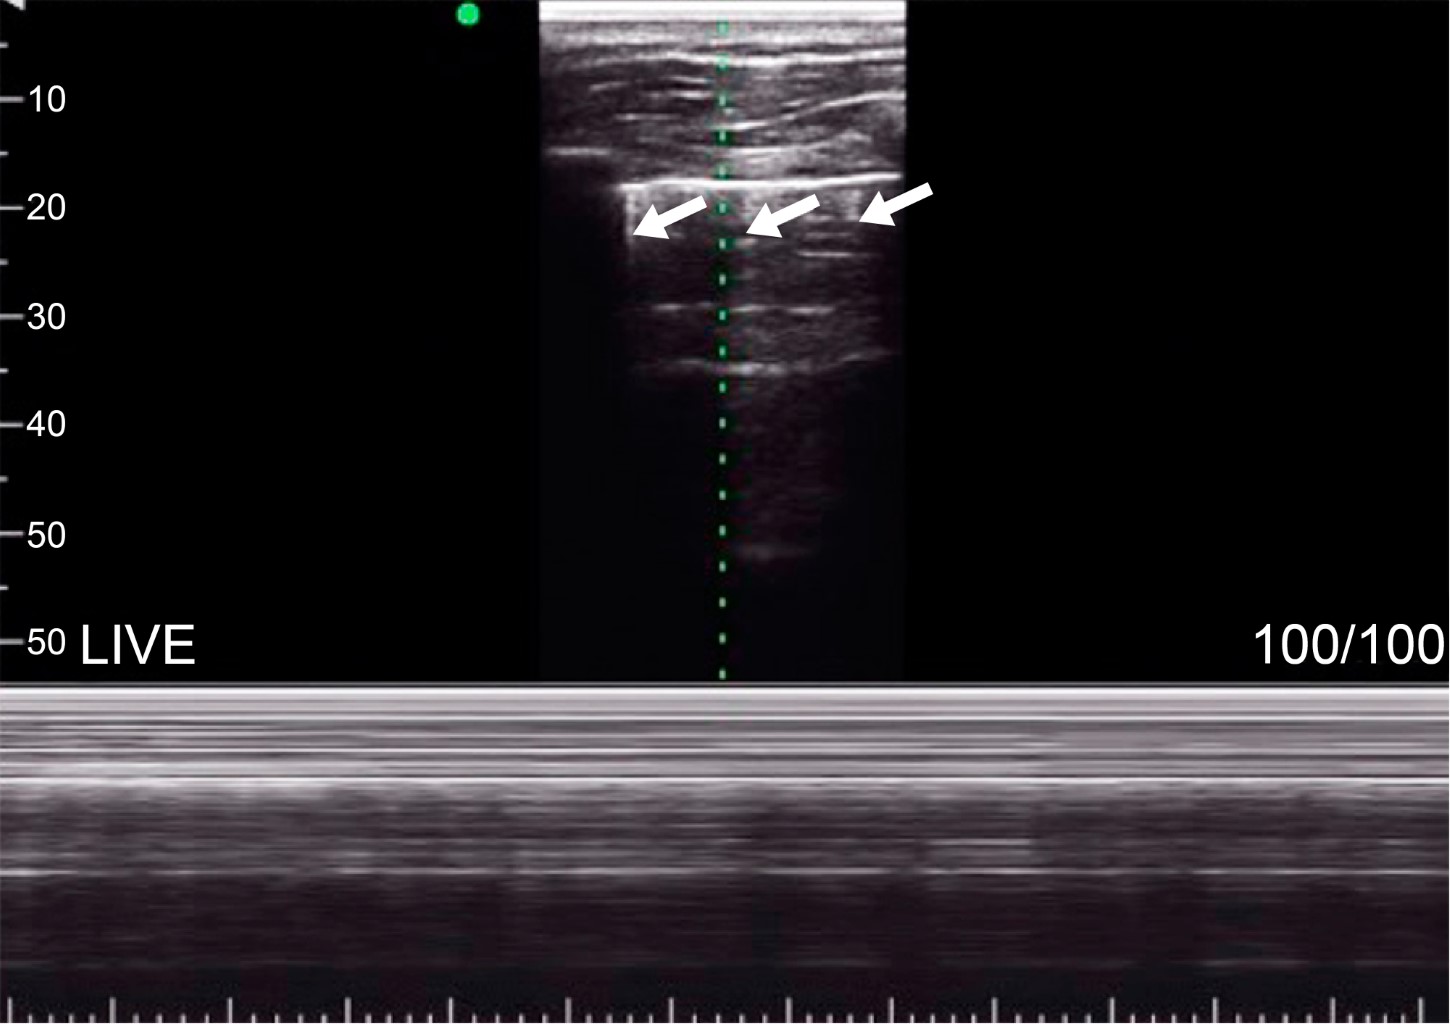

Relationship of total electrolyte balance with the appearance of A and B lines during the perioperative period in patients undergoing surgery under general anesthesia at the Nuevo Sanatorio Durango

water balance, A lines, B lines, general anesthesia.

Introduction: the optimal management of intravenous intraoperative fluids is critical since insufficient and excessive resuscitation is associated with damage. Due to this, lung ultrasound monitoring is positioned as an essential method to guide fluid resuscitation. Objective: to understand the relationship between total fluid balance (TFB) and the appearance of lines A and B during the perioperative period in patients undergoing surgery under general anesthesia. Material and methods: a prospective, longitudinal, and observational study was carried out. TFB was quantified throughout the surgery, and the amount of fluid was assessed by pulmonary ultrasound, identifying the appearance of lines A and B. Results: the sample was made up of 50 patients. A statistically significant relationship was observed between the appearance of A-lines and TFB (p = 0.009), a situation that did not occur between TFB, and the appearance of B lines (p = 0.503). An association was found between BMI and the appearance of B lines (p = 0.001). Conclusions: the evidence suggests that the appearance of B lines can help determine if overhydration has been entered in obese patients.

Figure 1